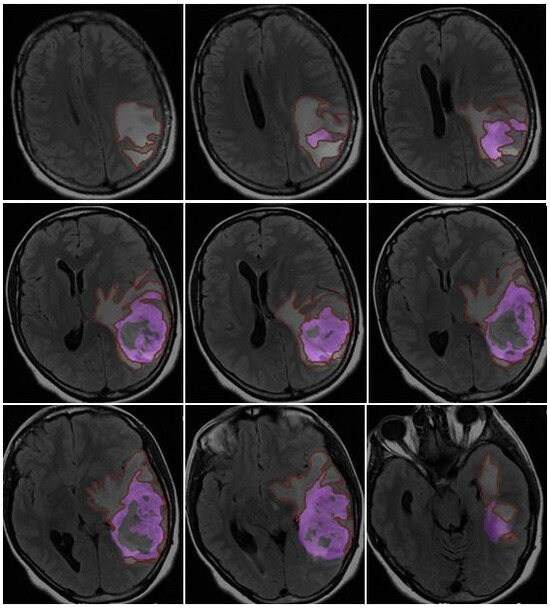

- Morphological appearance: We divided GB lesions into three categories based on the enhancing wall thickness: thin, <3 mm; thin-nodular, when the enhancing wall showed focal thickenings > 3 mm; and nodular, when solid appearance was predominant and intratumoral necrosis was absent or <1.5 cm3. A total of 11 (13%) masses showed a thin pattern, 51 (58%) showed a thin-nodular pattern, and 25 (29%) showed a nodular pattern.

3.2. Quantitative Analysis